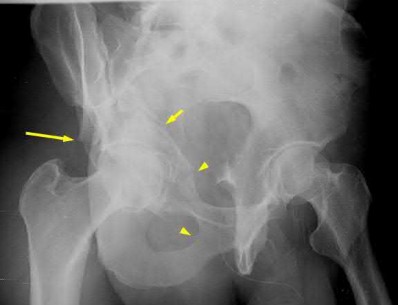

Figures A-C: The initial radiographs reveal the posterior subluxation of the talus with associated posterior subluxation of the fibula without significant coronal plane deformity. This deformity should raise the suspicion of a Bosworth fracture-dislocation, especially if closed reduction is not successful. Figures D and E: Axial CT images demonstrating Bosworth fracture-dislocation of the fibula entrapped behind the tibia. Also, note the fracture extension to the posteromedial rim in this posterior pilon variant.

Figure F: Positioning of the plate suggests a posterolateral approach to address both the fibula and posterior malleolus fractures.